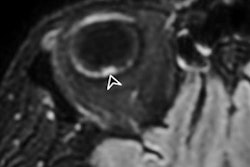

MRI demonstrated findings consistent with acute infarction without microhemorrhages (a, b, and c), along with focal irregular narrowing and banding of the proximal M1 segment of the left middle cerebral artery with a slightly reduced distal flow (d), according to Mirzaee and colleagues. Images courtesy of the RSNA.There are many reasons for stroke in children, ranging from "arterial dissection, embolic or thrombotic stroke, cerebral vasculitis in the context of systemic disease (including Kawasaki disease), and genetic disorders with arteriopathy," Mirzaee and colleagues wrote. Yet their best diagnosis was that the child's stroke had been caused by focal cerebral arteriopathy.